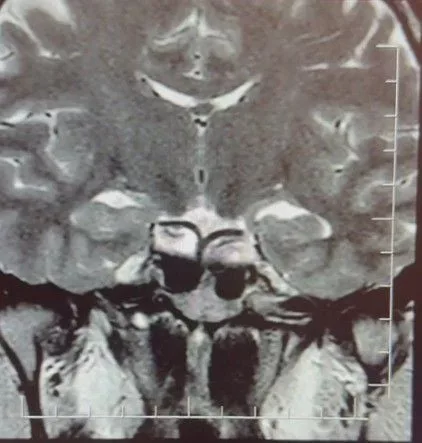

Yapılan ileri tetkiklerde hastaya hipofiz MR çekildiğini aktaran Çiftçoğlu, "MR sonucunda beynin hipofiz bölgesinde 'prolaktinoma' olarak adlandırılan bir tümör tespit ettik. Bu tümör, prolaktin hormonunun aşırı salgılanmasına neden oluyor. Genellikle iyi huylu olup ilaç tedavisiyle kontrol altına alınabiliyor" diye konuştu.

Gebelik belirtilerine benzer şikayetlerin farklı hastalıkların habercisi olabileceğine dikkat çeken Çiftçoğlu, "Prolaktin hormonu aslında beyinde hipofiz bezinden salgılanan ve süt salınımını sağlayan hormondur. Bunun yüksek olduğunu tespit ettikten sonra hastada hipofiz MR çektirdik. Çektiğimiz beyin MR'ında hastanın hipofiz dediğimiz bölgede kitleyi tümörü tespit ettik. Prolaktinoma dediğimiz bir tümör. Prolaktinoma tümörü beyinde hipofiz bölgesinde bulunmakta olup prolaktin hormonunun aşırı miktarda salgılanmasını sağlayan bir tümördür. Bu durumda iyi huyludur, kanserleşme olmasını çok yoktur. Dolayısıyla ilaçla tedavisi mümkündür ama gebelik şikayetlerini de andırdığı için mutlaka ayırıcı tanıda akılda tutulması gereken bir durumdur. Hasta da bizle öğrendi 'hamileyim' diye geldi hasta, gebelik muayenesi olma talebiyle geldi ancak biz tümörü tespit ettik. Önce gebe olmadığını tespit ettik ve sonra 'Bu şikayetlere sebep olabilecek ne var?' diye araştırdığımızda bu durum ortaya çıktı. Yani tümörü de aynı gün içerisinde değil birkaç gün sonra ileri tetkik sayesinde öğrenmiş oldu" dedi.